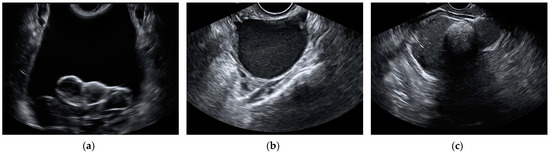

The most frequent histological type in false-positive cases by the aggregate model were cystadenomas and endometriomas. In total, 14 cystadenomas and 14 endometriomas were wrongfully classified as malignant by the model. Additionally, 10 cystadenomas and 5 endometriomas were also misclassified as malignant by subjective assessment. Out of these, eight cystadenomas and four endometriomas were misclassified by both the aggregate model and the SA. The total amount of mislabeled cases by the model was calculated as the sum of false positives and false negatives, added over all k-folds. The histopathology of misclassified cases by the aggregate model and subjective assessment can be found in Table 5. Ultrasound images of misclassified images by the CNNs can be found in Figure 5 and Figure 6.

Figure 5.

Still ultrasound images of malignant ovarian masses misclassified as benign by the aggregate model. (a) Endometrioid ovarian carcinoma, (b) high-grade serous ovarian carcinoma, and (c) high-grade serous ovarian carcinoma.